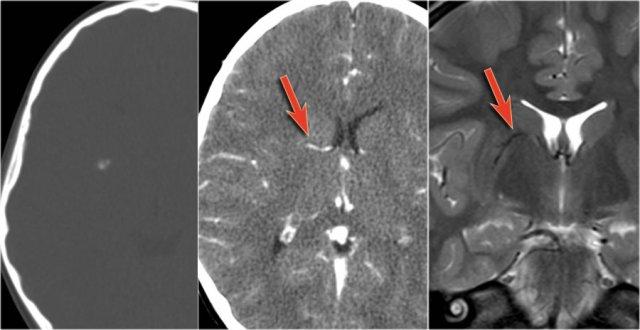

Một người đi xe đạp 46 tuổi nhập viện với triệu chứng co giật sau khi bị xe ô tô đâm.

Hình ảnh CT chỉ cho thấy xuất huyết dưới nhện tối thiểu (mũi tên).

MRI được thực hiện vài tuần sau chấn thương do bệnh nhân có thay đổi nhân cách.

Chuỗi xung T2* cho thấy nhiều ổ lắng đọng hemosiderin tại vùng ranh giới giữa chất xám và chất trắng, phù hợp với tổn thương sợi trục lan tỏa (DAI).

Lưu ý vị trí của các vi xuất huyết này khác với các ổ xuất huyết CAA nằm ở ngoại vi.